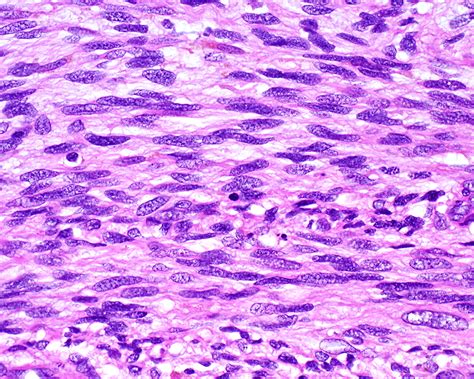

Spindle Cell Carcinoma is a rare histological subtype of squamous cell carcinoma (SCC). The term "spindle cell" refers to the morphological transformation of cancer cells that have lost their typical epithelial features and gained a mesenchymal (spindle-shaped) appearance. This process, often referred to as epithelial-mesenchymal transition (EMT), contributes to the tumor's aggressive biological behavior and its tendency for local invasion and rapid growth.

These tumors can arise in various anatomical locations, including the head and neck, the skin, the esophagus, and the respiratory tract. Because the cells appear non-epithelial under a microscope, pathologists often rely on specialized immunohistochemistry stains to confirm the diagnosis and distinguish it from other conditions like sarcomas or melanomas.